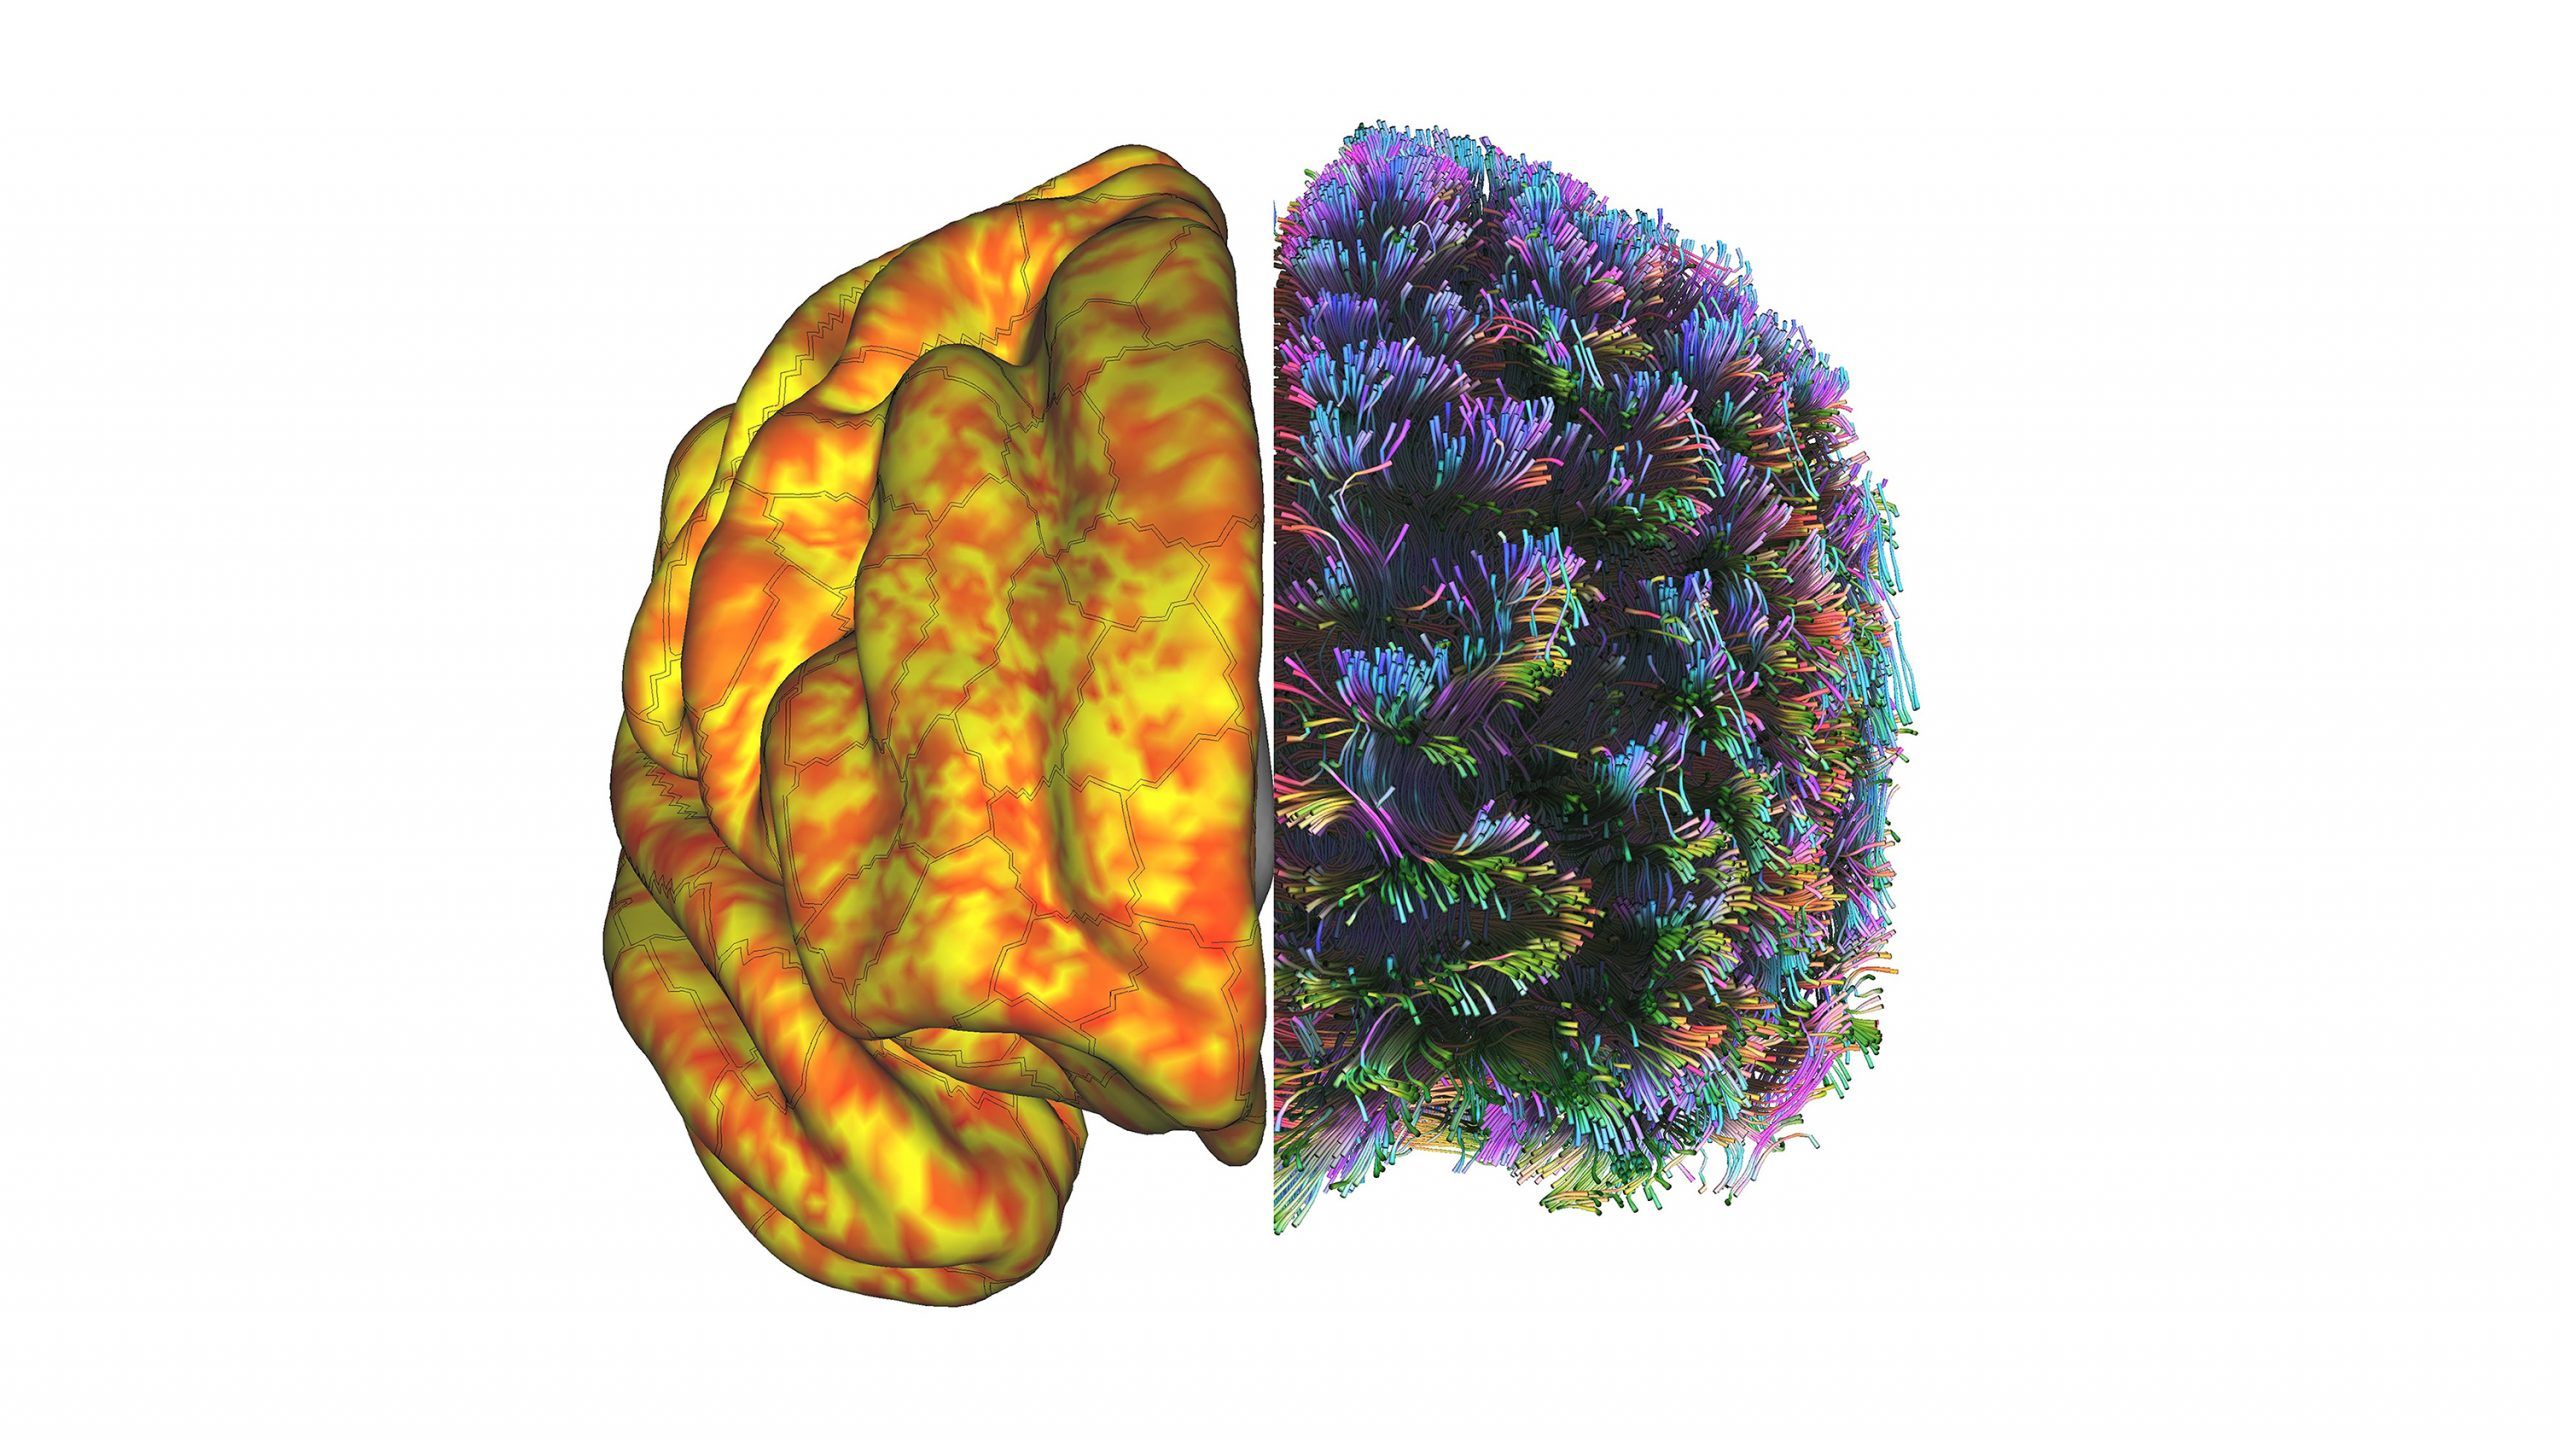

Above on the left is a map Monroe generated of the grey matter surface of a subject’s brain. Areas in orange are functionally connected while the subject is in a resting state. On the right is a diagram of how deeper, white matter fibers connect different parts of the brain. Monroe is interested in how exercise shapes brains. For example, Monroe and Dr. Donna Duffy in kinesiology found that roller derby athletes at rest exhibit unique brain patterns.